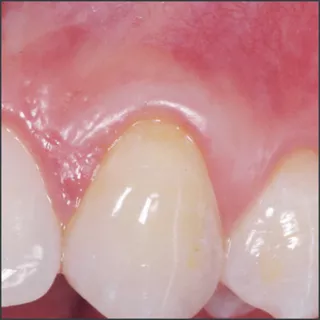

Before treatment with Straumann® Emdogain®.

Courtesy of Prof. Giovanni Zucchelli

8 months after treatment with Straumann® Emdogain®.